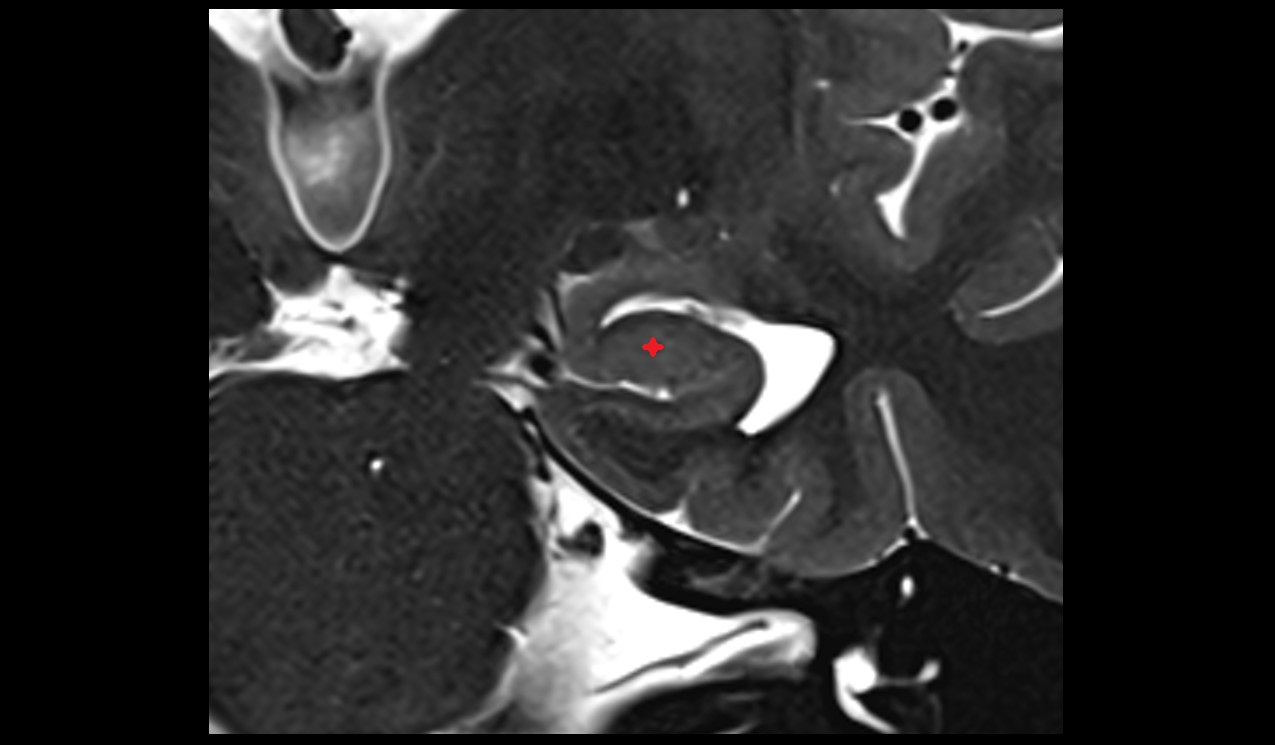

- Peripheral zone of prostate

- Anterior Fibromuscular Stroma of prostate

- Central zone of prostate

- Transitional zone of prostate